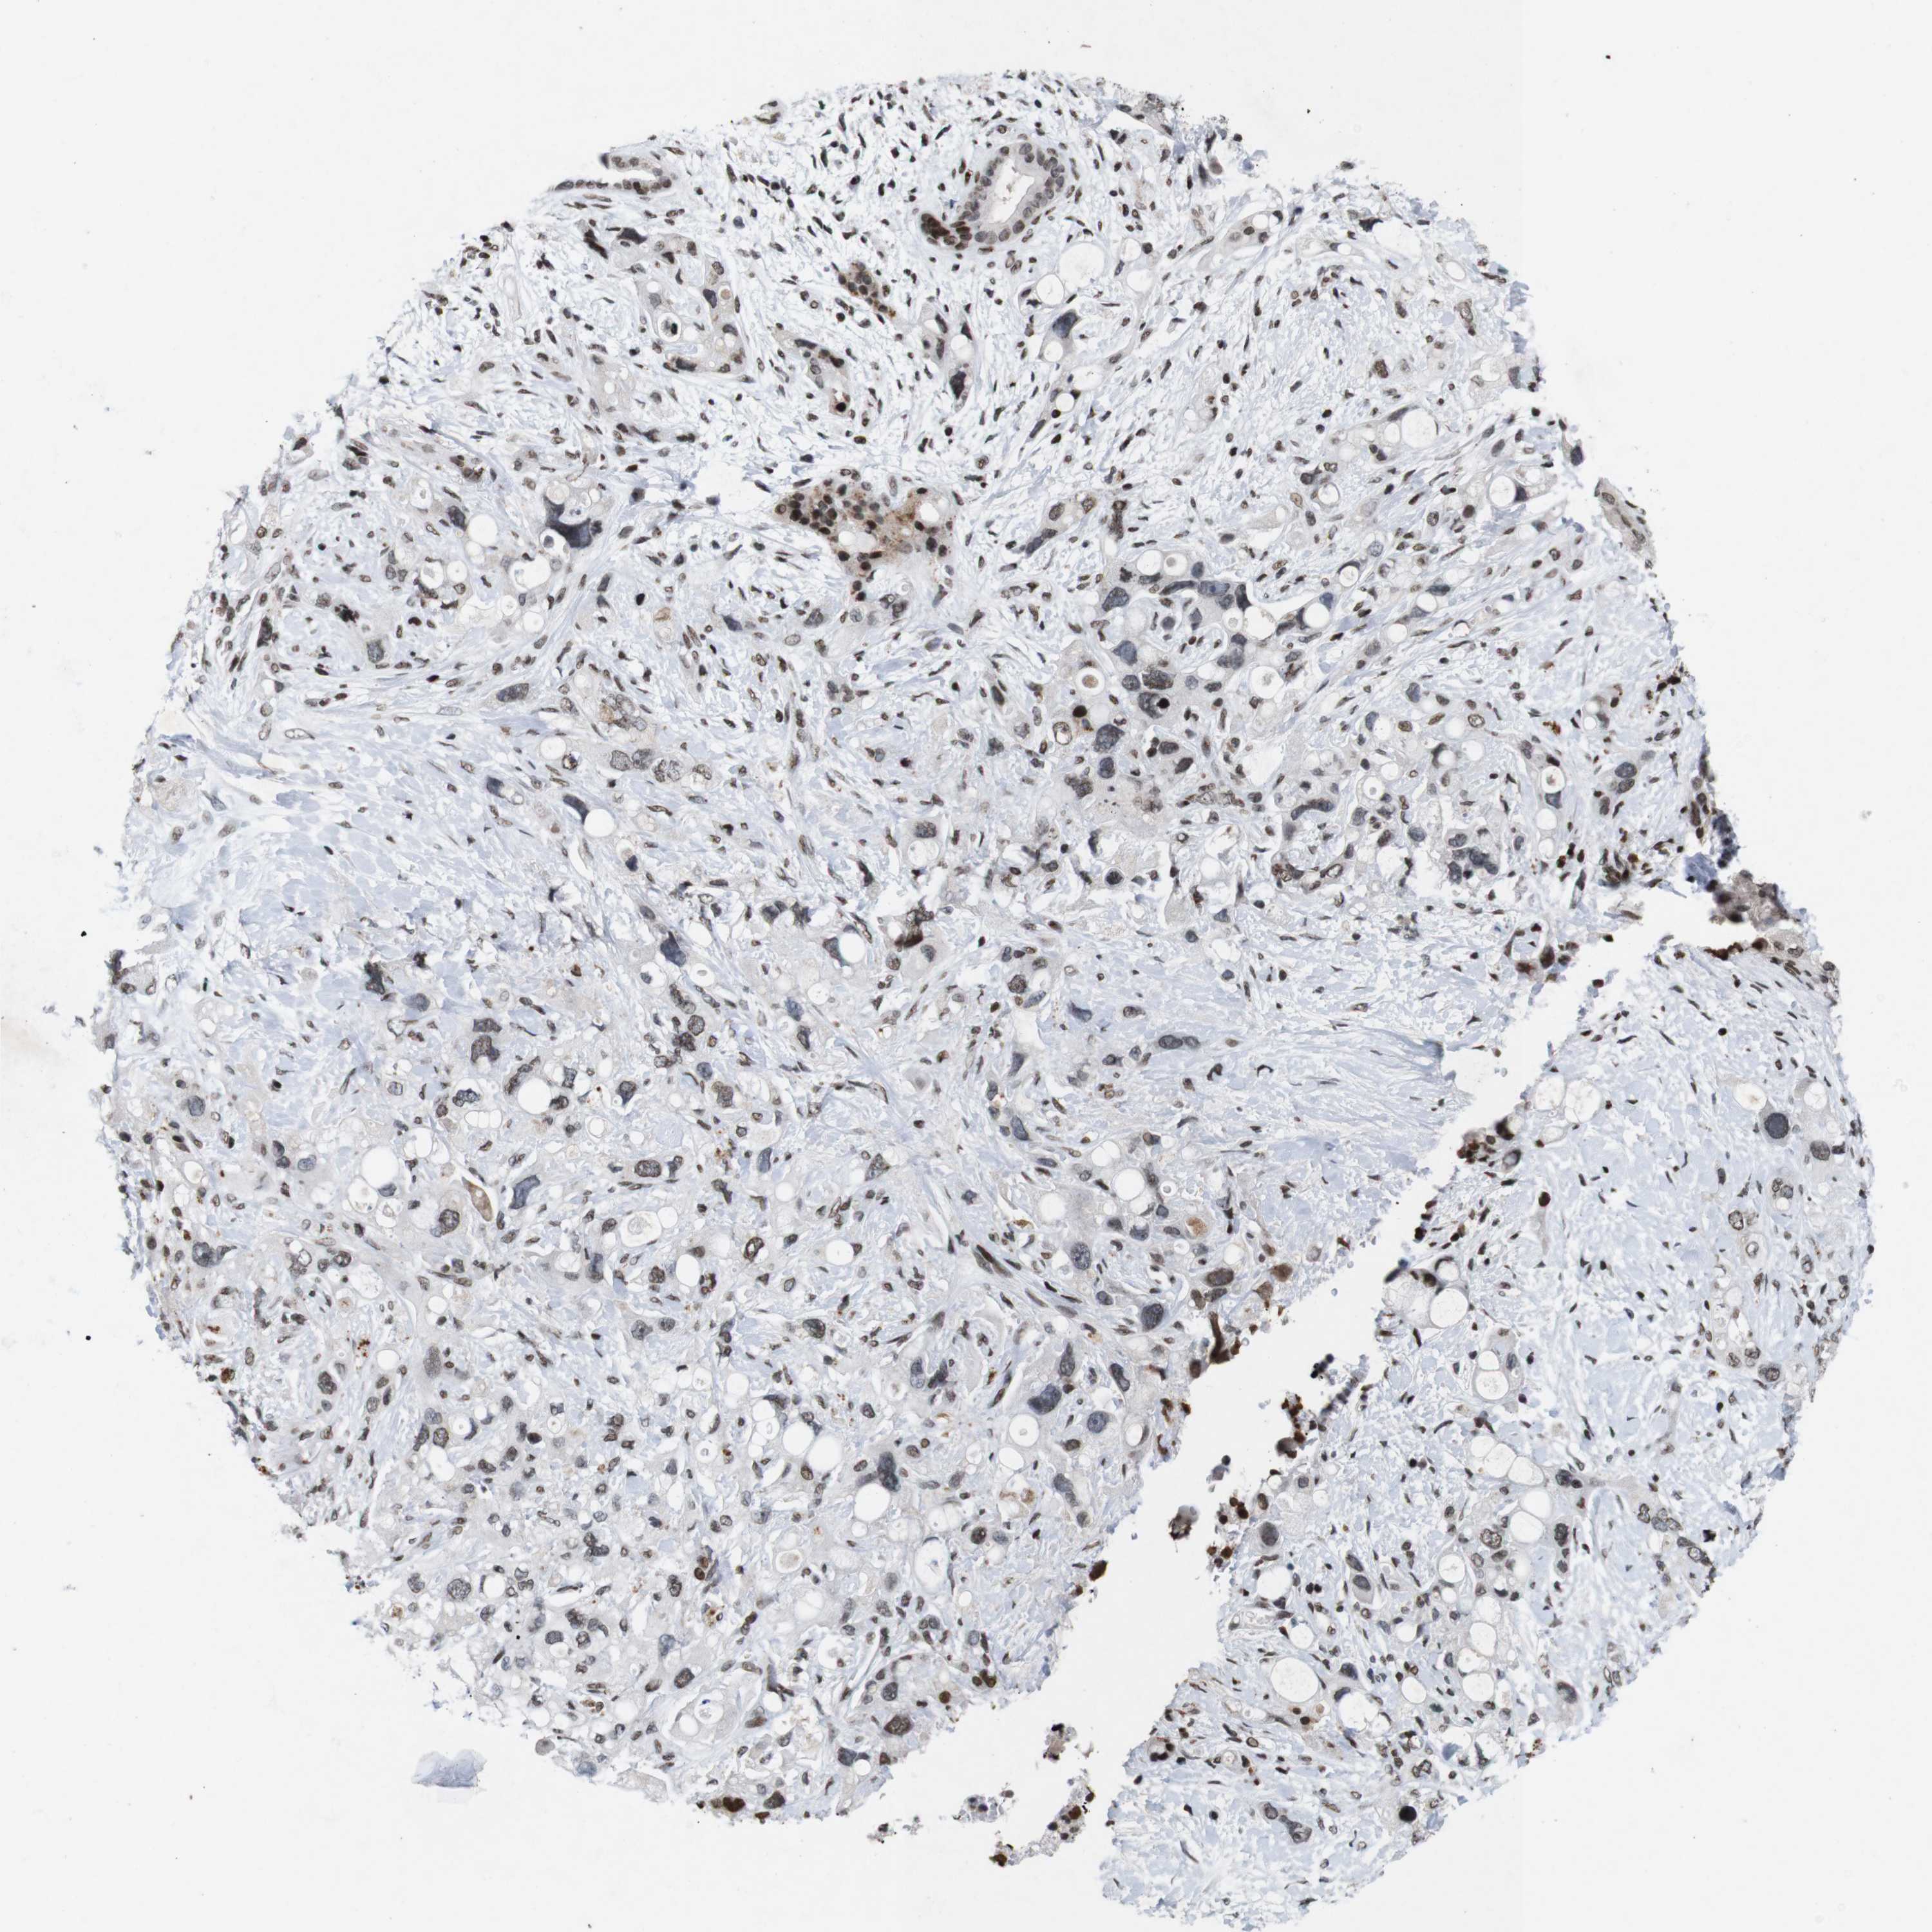

PANCREATIC CANCER - Protein expressioni

A mouse-over function shows sample information and annotation data. Click on an image to view it in a full screen mode. Samples can be filtered based on level of antibody staining by selecting one or several of the following categories: high, medium, low and not detected. The assay and annotation is described here.

Note that samples used for immunohistochemistry by the Human Protein Atlas do not correspond to samples in the TCGA dataset.

Antibody stainingi

Antibody staining in the annotated cell types in the current human tissue is reported as not detected, low, medium, or high, based on conventional immunohistochemistry profiling in selected tissues. This score is based on the combination of the staining intensity and fraction of stained cells.

Each image is clickable and will lead to virtual microscopy that enables deeper exploration of all samples and also displays staining intensity scores, fraction scores and subcellular localization as well as patient and tissue information for each sample.

Antibody HPA011324

Staining

High

Medium

Low

Not detected

Intensity

Strong

Moderate

Weak

Negative

Quantity

>75%

75%-25%

<25%

None

Location

Nuclear

Cytoplasmic/membranous

Cytoplasmic/membranous,nuclear

Adenocarcinoma, NOS